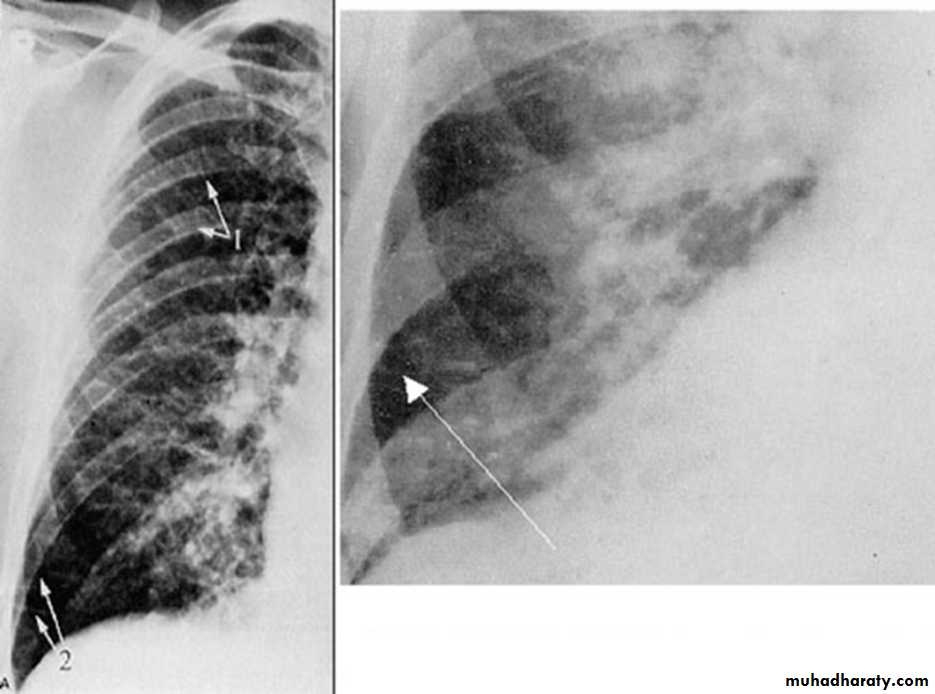

BNP brain natriuretic pepetideChest X-ray in Heart Failure

CardiomegalyCephalization of the pulmonary vessels

Kerley B-lines

Pleural effusions

Cardiomegaly Pulmonary vessel congestion

Pulmonary Edema due to Heart Failure

Kerley B lines